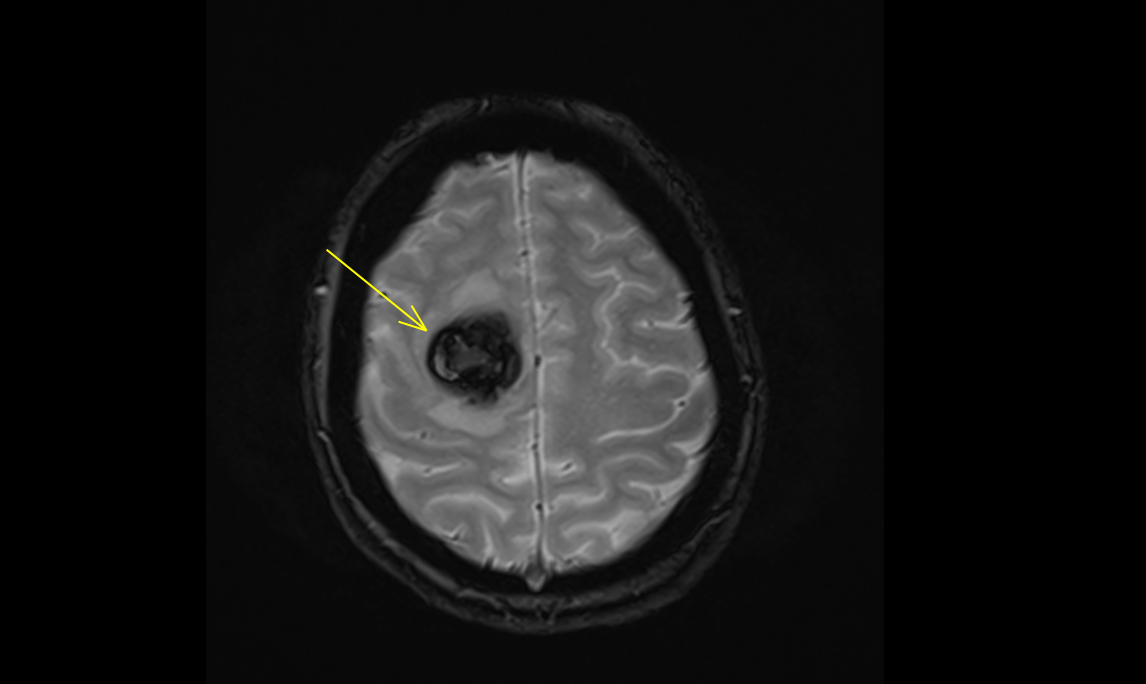

cavernome temporal

Figure 1. Cavernome temporal ayant saigné, en pré-opératoire